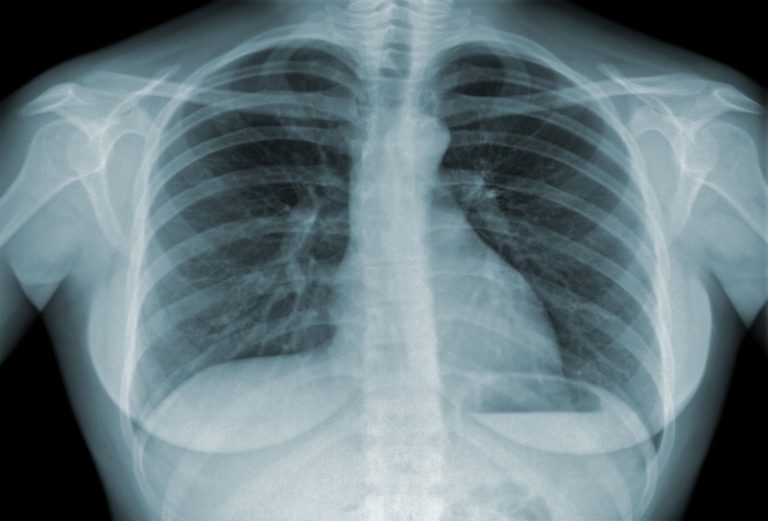

O diagnóstico é feito com base no exame físico, radiografia, tomografia, ultrassom de tórax e, principalmente, na toracocentese, que consiste na retirada de parte do líquido para análise laboratorial.

Esse estudo identifica sinais de infecção, células tumorais, presença de proteínas e outras informações que ajudam a compreender a causa do problema. É a análise do líquido que muitas vezes confirma se o derrame pleural é grave, já que revela diretamente a natureza da doença associada.